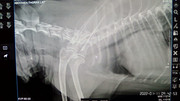

Коллапс трахеи форум